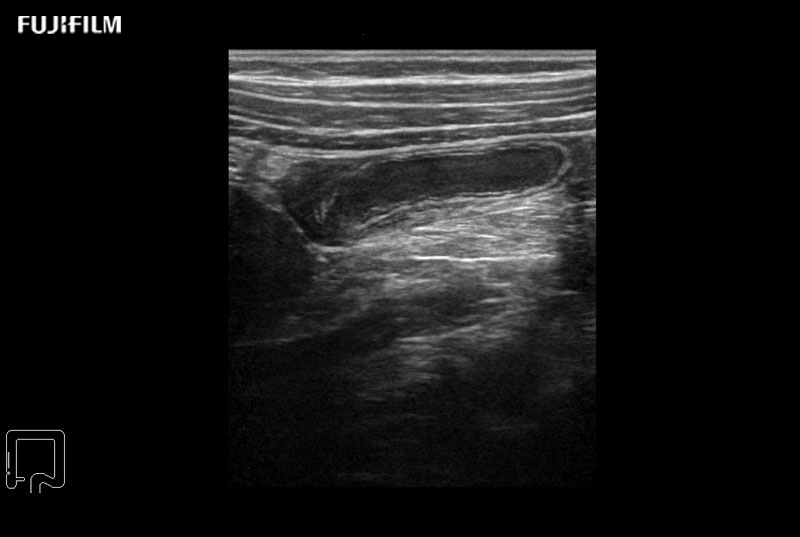

Spinal Procedure using L53K

Hockey-stick linear array transducer is the transducer of choice for spinal scanning, providing exceptional near and far-field resolution. Its low profile design lends itself perfectly to the spatial confines of spinal surgery.